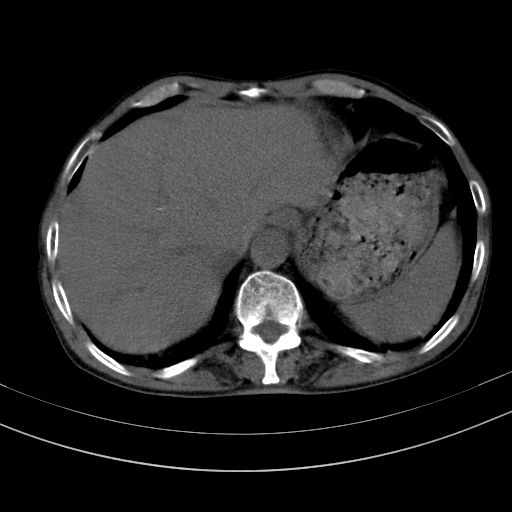

以下是引用dyqct在2010-1-9 17:56:00的发言:[br]考虑:1.双肾囊肿,左肾积水结石、旋转不良。[br] 2.右侧腹直肌血肿或纤维瘤。[br]肠道准备不好。做个增强。